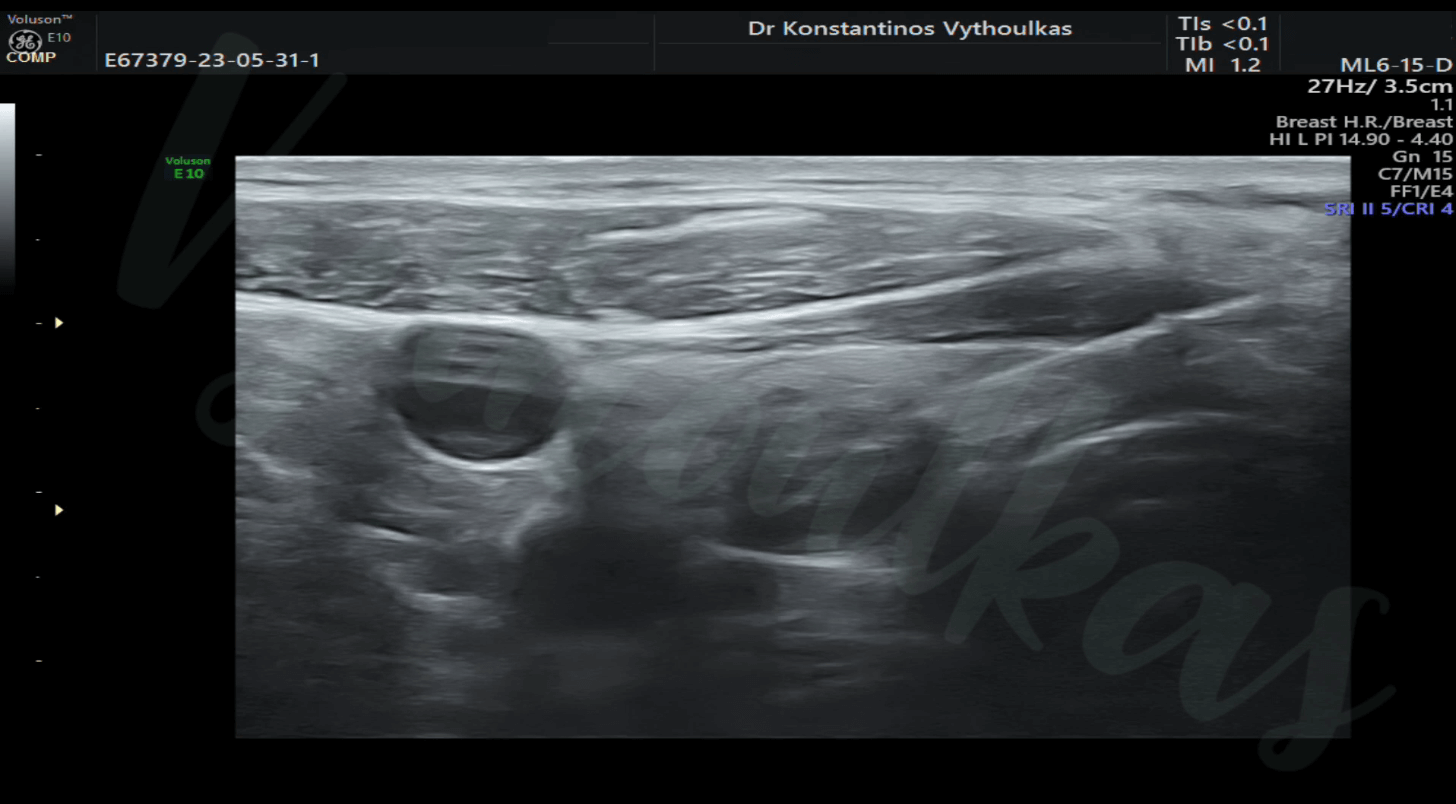

- FNAC μαστού Η κυτταρολογική αναρρόφηση με βελόνα (FNAC) κυστικών ή συμπαγών αλλοιώσεων μαστού είναι μια ελάχιστα επεμβατική χαμηλού κόστους τεχνική ιατρείου με τις εξής ενδείξεις: